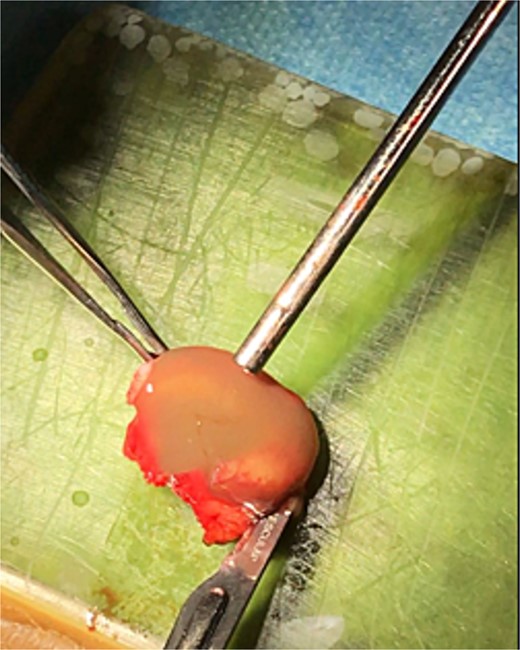

Open rhinoplasty was performed using a Goodman incision and elevation of the skin flap over the alar cartilages, supratip, and nasal dorsum for cyst excision and defect reconstruction with costal cartilage grafts. Dissection revealed a cystic lesion between the upper and lower lateral cartilages, as well as a unique bone attachment measuring ~2 cm × 0.8 cm on the left side (Figs 4 and 5). The cyst and attached bony fragment were excised en bloc to preserve structural integrity (Video S1). In particular, the septum cartilage was not visualized during dissection. A 3 cm costal cartilage graft, harvested from the fifth rib using the oblique split technique, was used to repair the defect. Costal cartilage slices were sutured with 4.0 Prolene as extension grafts to the nasal bone through preexisting turndown holes. Additional costal cartilage slices were interposed inferiorly to create a robust L-strut, then secured using 5.0 Prolene that was passed through a predrilled opening in the exposed nasal spine. Alar cartilages that had been over-resected were reconstructed using costal cartilage grafts. Diced costal cartilage was utilized, mixed with patient’s venous blood, to form a composite graft; This composite graft was wrapped in absorbable oxidized regenerated cellulose (Surgicel, Ethicon, USA) and placed for optimal support. Finally, a cap graft was placed on the tip apex and a strut graft of the alar cartilage was sutured between the medial crura (Figs 6 and 7) The patient reported no functional or aesthetic concerns during the postoperative period.

Total excision of the cystic content using an open rhinoplasty approach.